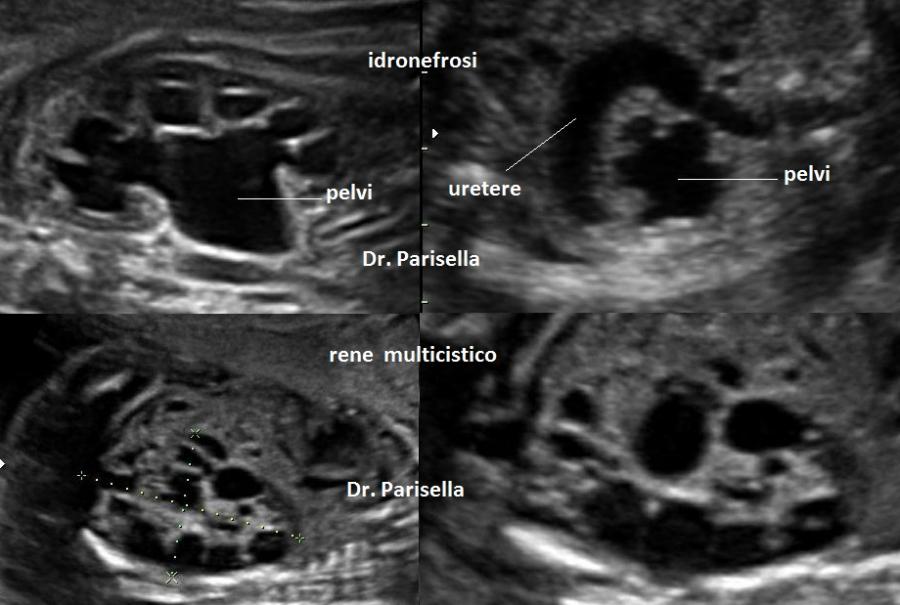

All'ecografia prenatale si riscontra ipoplasia toracica (torace stretto e coste corte), rizomelia lieve-moderata e frequentemente  displasia renale policistica.